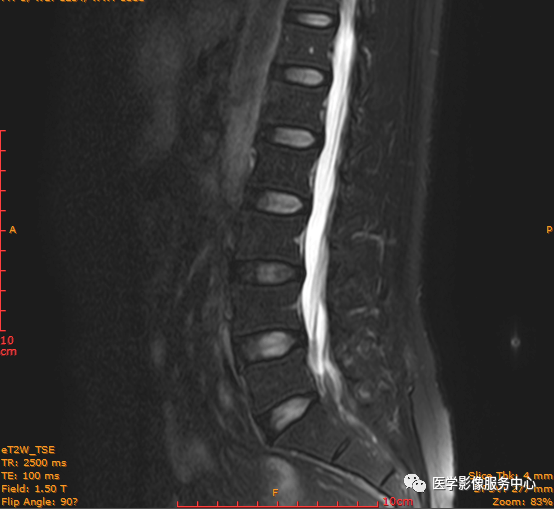

临床诊断 :腰突症?故行腰椎MRI检查,图像如下:

矢状位PD压脂序列

这个患者腰椎间盘膨出程度不明显,神经根没有明显的受压,椎管未见明显狭窄,那这个患者腰疼的“罪魁祸首”是腰椎间盘膨出嘛?

大家有没有留意到还有哪个地方不正常呢?

L3-4椎间盘后缘可见点状高信号区(红色箭头所指处)

红色箭头所指的异常信号区是是什么呢?平时工作中大家有没有遇到这种情况,你会不会忽略这个异常信号?有没有想过这个椎间盘后缘高信号区是引起患者腰疼的重要因素呢?下面为大家重点介绍。